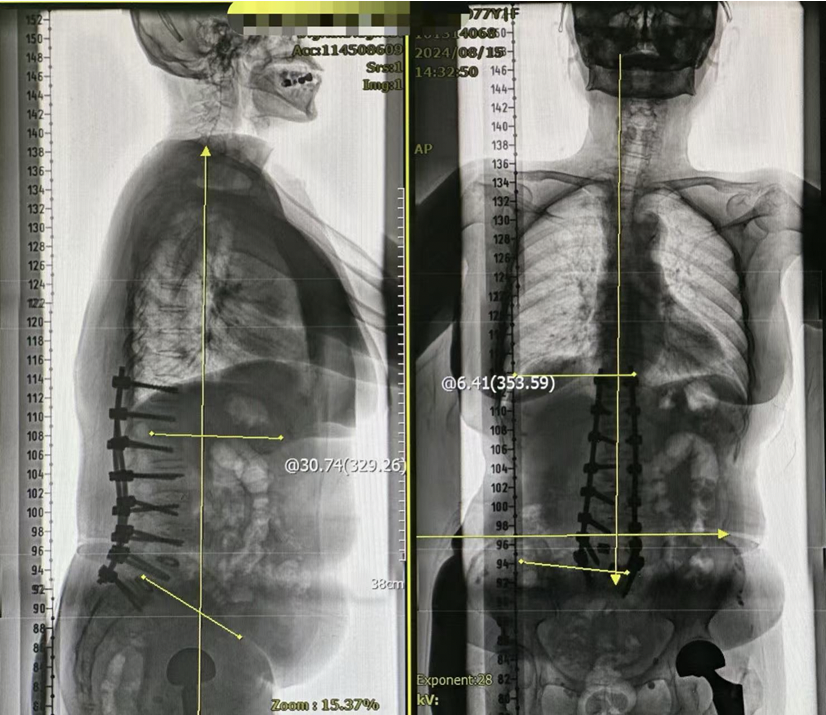

术后影像

本例患者术前保守治疗2年,均无法明显缓解症状,且活动能力进行性下降,期间因日常活动不能自己,不慎 摔倒致股骨颈骨折,随后进行了股骨头置换手术。医疗团队通过对该例患者脊柱T11-S1节段进行脊柱矫形手术, 术后侧弯角度矫正为6.4°。术后患者自诉腰背部疼痛、活动受限等症状改善明显,基本可以独立自主生活,完成 散步、上下楼梯等活动。